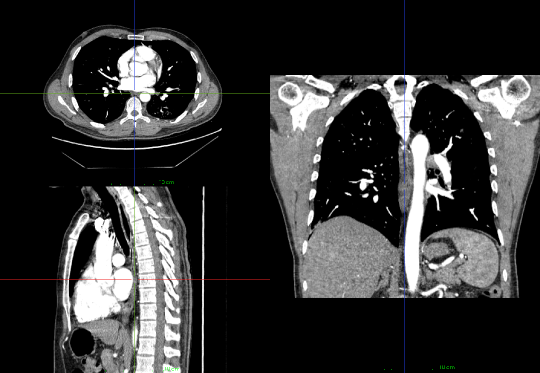

Appendix E Example of CTPA scan

For the readers who are unfamiliar with CTPA, we also attached an example in Figure 9. This scan demonstrates an MPR (multi-planar reconstruction) format rendering of the 3D volumetric CTPA scan from our INSPECT cohort.

Refer to caption

Figure 9: An example of CTPA examination scan in multi-planar reconstruction